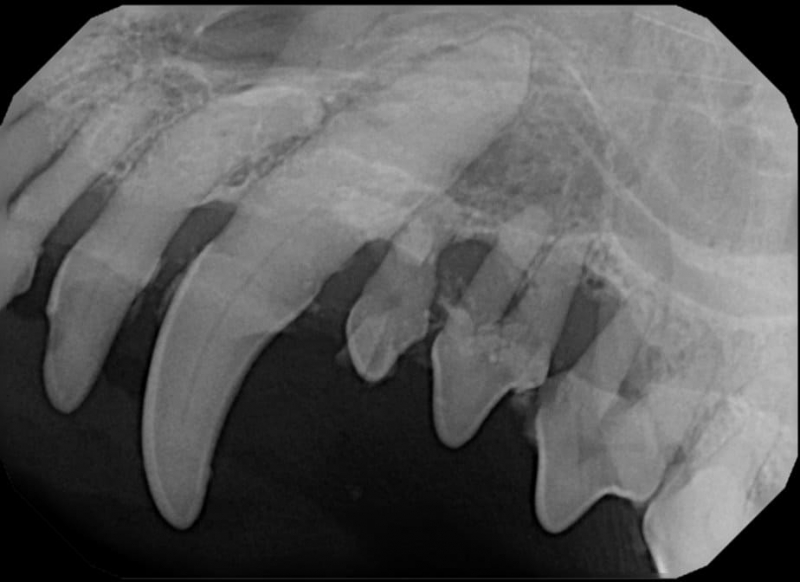

Tooth resorption is a disease process where the body begins to break down the adult tooth. It is widely known to occur in cats but can also occur in dogs. In cats these lesions are thought to be inflammatory, while in dogs they can be more of a replacement resorption process. These lesions can be very painful and should be treated, generally with extraction depending on the type of resorption that is occurring. The disease can be progressive and affect many teeth over several years. It is important to have regular checkups and yearly dental cleanings to monitor for these lesions.

Periodontal disease is extremely common in dogs and cats. Over 80% of dogs and cats over two years of age have some degree of periodontal disease. Periodontal disease is best prevented by yearly professional dental cleanings starting at two years of age and at home brushing at least three times weekly. Brushing should begin at a very early age to allow your new pet to get used to regular brushing. In severe cases of infection or periodontal disease, the teeth may need to be surgically extracted. Extractions should always involve x-rays of the tooth first, as many teeth have multiple roots or may be diseased below where the eye can see. Extracting larger teeth in animals requires oral surgery, equivalent to removing wisdom teeth in people. It is vital that all of the tooth and roots be removed for the periodontal infection to resolve. In cases of important teeth with mild to moderate periodontal disease, multiple periodontal treatments can be offered to help save these teeth.